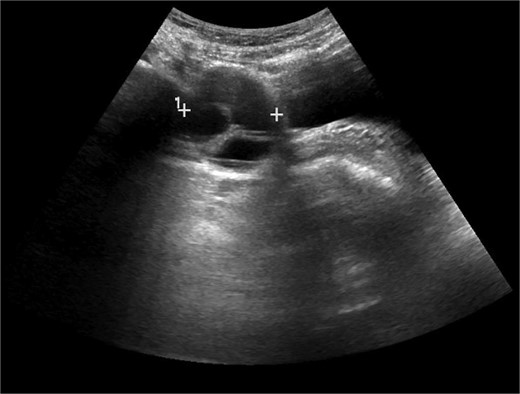

A 40-year-old P4 woman, with a past medical history of celiac disease, hypothyroidism, and varicose veins, presented with intermittent right lower quadrant pain that occurs 1–2 times per week for over a year, exacerbated by sexual activity. She denied any changes in urinary habits, bowel movements, or early satiety. Transvaginal ultrasound measured the right ovary at 4.5 × 4.3 × 3.8 cm with a complex cyst measuring 4.6 × 3.3 × 3.6 cm and containing several cystic spaces with low-level internal echoes. Prior imaging showed the cyst had been slowly growing with dimensions from one year ago (Fig. 1) at 4.2 × 3.7 × 3.6 cm and three years ago at 2.8 × 2.1 × 1.6 cm. Magnetic resonance imaging (MRI) of the pelvis (Fig. 2) revealed a complex solid and cystic retroperitoneal mass abutting the right external iliac vessel. Although the patient reported only intermittent pain at this time, the continued increase in size was concerning for a potential neoplasm. Although malignancy could not be ruled out, the absence of elevated tumor markers like CA-125 suggested a benign finding. The decision was made to proceed with diagnostic laparoscopy for suspicion of growing ovarian lesion. The diagnostic laparoscopy successfully visualized normal-appearing ovaries and fallopian tubes bilaterally. However, a 4-cm firm, circumferential retroperitoneal mass within the right broad ligament along the sidewall of the pelvis was discovered. Due to the mass’s location and proximity to the right ureter and uterine artery, dissection was not attempted in favor of conservative treatment and monitoring.

Transvaginal ultrasound image of right adnexa. Cystic structure with the measurement 4.2 × 3.7 × 3.6 cm at the time of imaging.